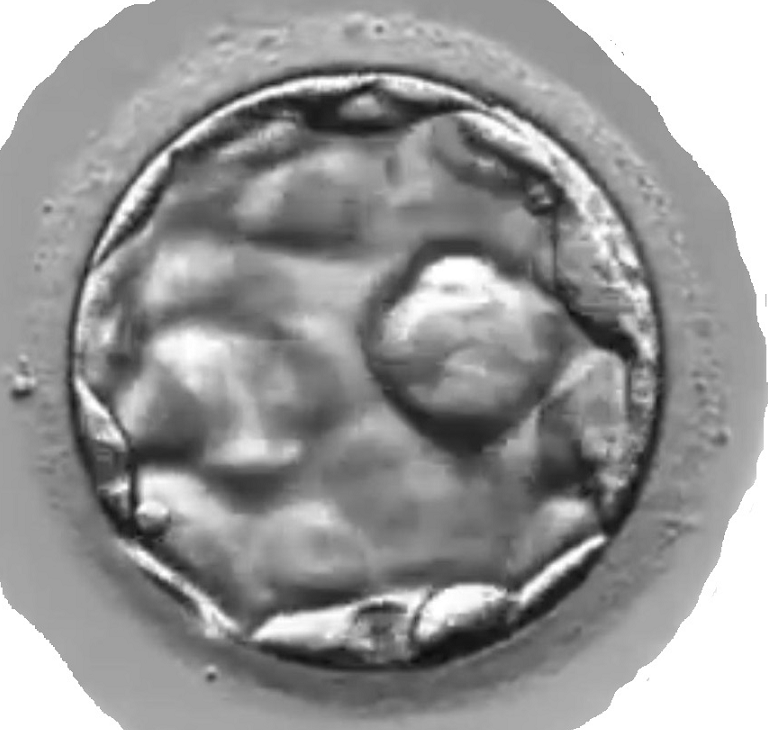

A human blastocyst that developed in SYNBIOS® SYNTHETIC EMBRYO CULTURE MEDIUM. Image was captured using the embryoscope. The workers noted that the performance of the SYNBIOS® SYNTHETIC EMBRYO CULTURE MEDIUM was comparable to contemporary conventional protein-containing medium. Courtesy: Yousef AlHelou, April 2020, Fakih IVF, United Arab Emirates.

A hatching human blastocyst that developed in SYNBIOS® SYNTHETIC EMBRYO CULTURE MEDIUM. Image was captured using the embryoscope. The hatching occurred naturally. The workers noted that the performance of the SYNBIOS® SYNTHETIC EMBRYO CULTURE MEDIUM was comparable to contemporary conventional protein-containing medium.

Courtesy: Yousef AlHelou, April 2020, Fakih IVF, United Arab Emirates.